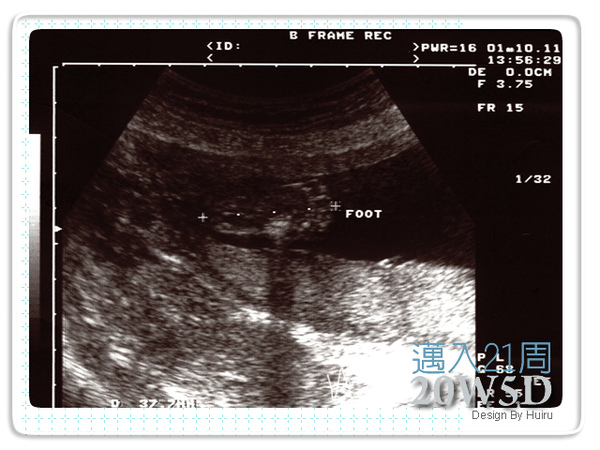

超音波裡的好正腳丫子非常的明顯,好幾個角度都可以看到他的腳丫在那動來動去,就這樣醫師照了很久,阿不過連我中間跟她說我是來看吃壞肚子的,她還是持續幫我觀察,看她好熱心喔,我就不打擾她了><。(我躺到都快睡著了= =)